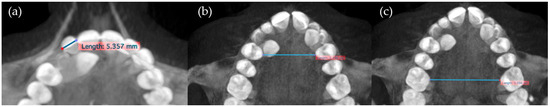

- Mesiodistal crown diameter of the lateral incisor (MD2) (Figure 4).

- Transverse distance between the palatal cusps of upper first premolars (1.4 and 2.4 teeth) (Transv4).

- Transverse distance between mesiopalatine cusps of upper first molars (1.6 and 2.6 teeth) (Transv6) (Figure 4).